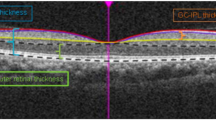

Optical coherence tomography

All eyes received macular and optic disc imaging using the Cirrus High Definition OCT (software version 5.0.0.326; Carl Zeiss Meditec, Dublin, CA). The scan speed for this spectral-domain OCT is 27,000 A-scans per second and the axial resolution is 5 μm42. Both the Optic Disc Cube 200 × 200 protocol and the Macular Cube 200 × 200 protocol were performed. Disc area generated by the Optic Disc Cube 200 × 200 protocol was recorded for subsequent analysis. The Macular Cube 200 × 200 protocol was used for macular thickness measurements in an area of 6 × 6 mm. Eye movements were checked by reviewing the line-scanning ophthalmoscope (LSO) fundus images. Images with misaligned vessels within the scanning area were excluded and retaken. All the included images had minimum signal strength of 7. Images with segmentation errors were excluded from the analysis (3.5%).

The Cirrus HD-OCT software was used to generate retinal thickness maps. The mean thickness was determined for nine retinal subfields in three concentric circles (with diameters of 1, 3, and 6 mm) centered at the fovea, as defined by the Early Treatment Diabetic Retinopathy Study (ETDRS). The retinal subfields in the retinal thickness map are central, inner superior, inner nasal, inner inferior, inner temporal, outer superior, outer nasal, outer inferior, and outer temporal. The central subfield thickness was defined by the innermost 1 mm diameter circle while the inner and outer subfields were bounded by the 1 and 3 and 3 and 6 mm diameter circles, respectively. Apart from the nine retinal subfields, the average of the four-quadrant macular thicknesses in the inner and outer rings was also calculated as average inner macular thickness and average outer macular thickness, respectively. Overall macular thickness in the entire grid area was also recorded from the retinal thickness maps.